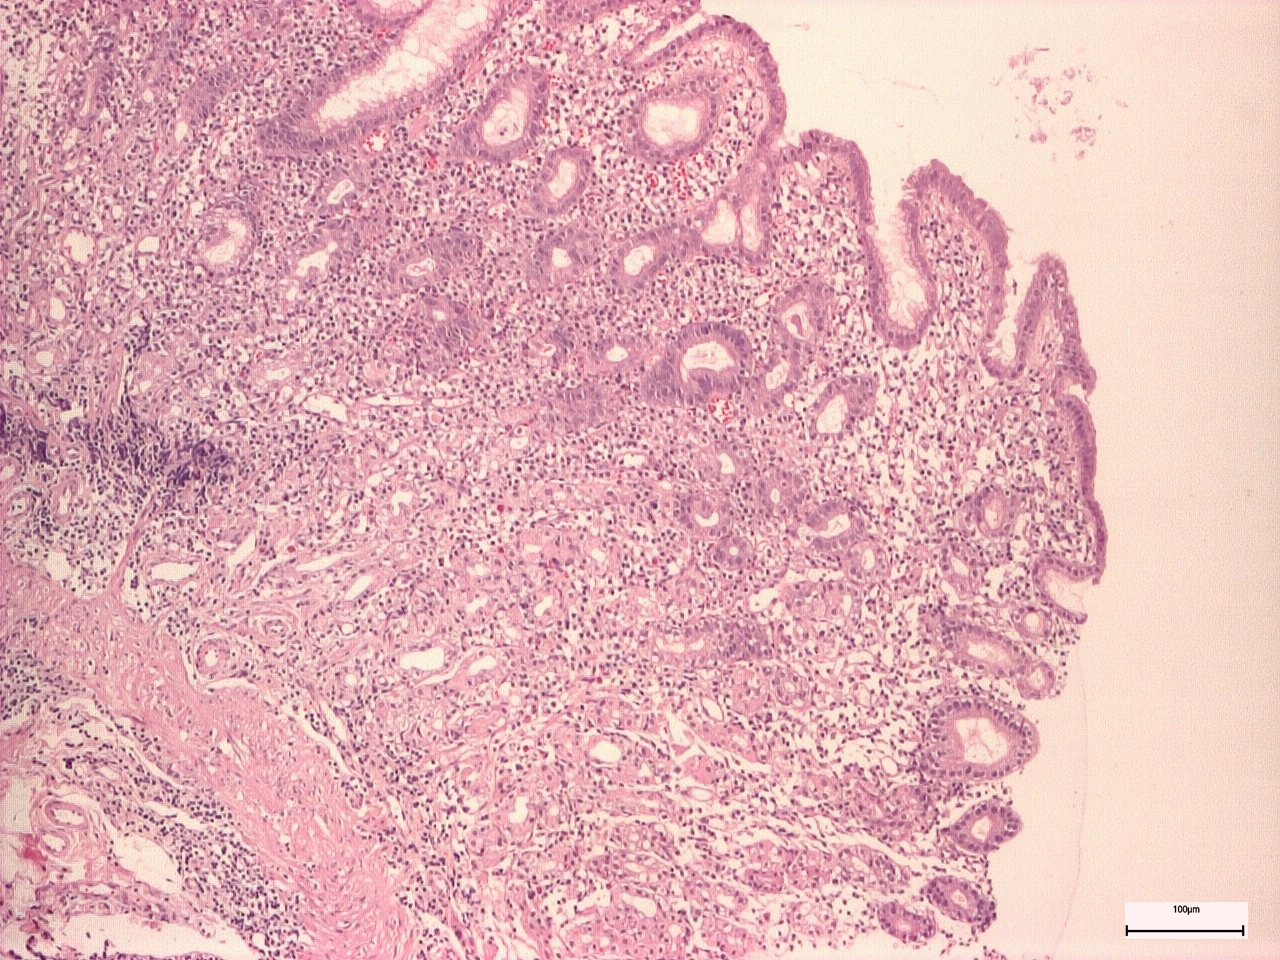

Non-active gastritis was diagnosed if chronic inflammation (represented by the presence of mononuclear and plasma cells within the lamina propria, but not neutrophils) was present. Active gastritis diagnosis was established if acute inflammatory cells were present in corporal and antral mucosa (Figure 3 and Figure 4) [8].

Figure 3. Antral active chronic gastritis.